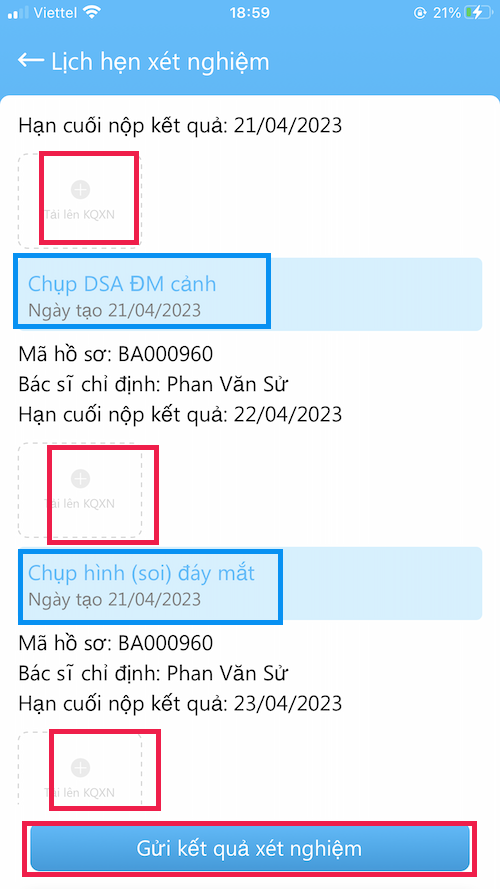

LỊCH HẸN XÉT NGHIỆM

Các xét nghiệm Bác sĩ yêu câù cần làm

- Nơi gởi kết quả cho Bác sĩ

- Các xét nghiệm trước đây cũng có thể xem tại đây

- Gởi kết quả xét nghiệm bằng hình ảnh ( chụp trực tiếp hoặc lấy từ thư viện ảnh)

- Hãy kiểm tra xét nghiệm mà Bác sĩ yêu cầu phải làm

- Trường hợp bệnh nhân chưa nhận được toa thuốc có thể do chưa làm xét nghiệm

GỞI XÉT NGHIỆM

Gởi xét nghiệm cho Bác sĩ

- Vào Tài khoản –> Lịch hẹn xét nghiệm

- Kết quả gởi bằng hình ảnh (chụp trực tiếp hoặc lấy từ thư viện)

- Nên làm theo đúng thời gian hẹn

- Có kết quả, Bác sĩ sẽ gởi toa thuốc

- Vì lý do nào đó, bệnh nhân không làm xét nghiệm, hãy gởi cho bác sĩ nội dung lý do chưa làm (chụp hình chữ viết)

- Bấm Gửi kết quả xét nghiệm khi đã tải hình kết quả lên

- Các xét nghiệm nên trao đổi với Bác sĩ khi khám bệnh

GỞI XÉT NGHIỆM

Gởi xét nghiệm cho Bác sĩ

- Vào Tài khoản –> Lịch hẹn xét nghiệm

- Kết quả gởi bằng hình ảnh (chụp trực tiếp hoặc lấy từ thư viện)

- Nên làm theo đúng thời gian hẹn

- Có kết quả, Bác sĩ sẽ gởi toa thuốc

- Vì lý do nào đó, bệnh nhân không làm xét nghiệm, hãy gởi cho bác sĩ nội dung lý do chưa làm (chụp hình chữ viết)

- Bấm Gửi kết quả xét nghiệm khi đã tải hình kết quả lên

- Các xét nghiệm nên trao đổi với Bác sĩ khi khám bệnh